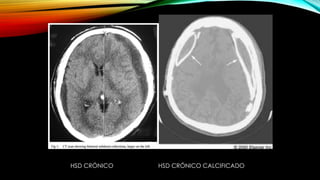

DIAGNÓSTICO DE HSD

• TAC craneal:

Agudo 1-3 dias Hiperdenso

Subagudo 4º dia- a 2-3 semanas Isodenso

Crónico > 3 semanas y < 3-4 meses Hipodenso similares a la

densidad del LCR

Despues de 1-2 meses Pueden ser lenticulares

(similares a los

epidurales) con

densidad > LCR y <

sangre nueva

HSD CRÓNICO HSD CRÓNICO CALCIFICADO